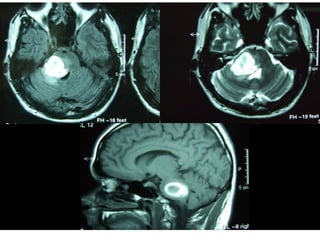

Absceso cerebral

Y cerebeloso.

Los cerebrales habitualmente asientan en el lóbulo

temporal y pueden ser de difícil diagnostico.

El paso de materia purulenta a la masa encefalica provoca, tanto en

el cerebro como en al cerebelo:

Primer

estadio.

•Descenso de la temperatura

•Fiebre con escalofríos.

•Somnolencia.

•Cefalea.

•Malestar.

•Dificultad para concentrarse.

Absceso cerebral IRM

Segundo

estadio

•Formación del absceso.

•Sin otros datos clínicos

durante semanas

Tercer

•Crecimiento del absceso.

•Signos de irritación focal.

•Puede haber perdida de

conciencia.

Cuarto

•Ruptura del absceso que

puede verter su contenido a los

ventrículos o a espacios

subaracnoideos, generalmente

con desenlace fatal.

El absceso cerebeloso da síntomas antes que el

cerebral, por lo que puede ser diagnosticado en un

estadio mas precoz.

Hay perdida de del tono muscular, ataxia y

adiadicocinesia.

El diagnostico se establece mediante RM. Es

fundamental llevarlo acabo en los primeros estadios.